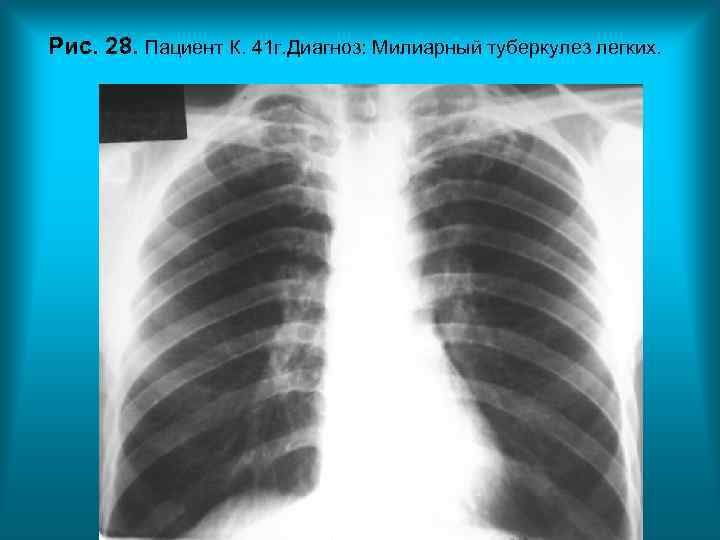

Рис. 28. Пациент К. 41 г. Диагноз: Милиарный туберкулез легких. Н. С. Воротынцева. С. С. Гольев Рентгенопульмонология